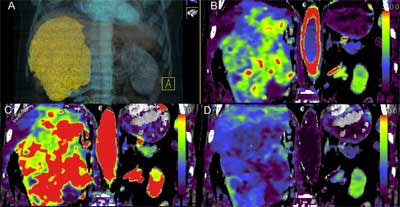

High-frequency volumetric helical perfusion CT imaging potentially has a higher radiation burden than single anatomical-level acquisitions. There has been concern regarding the radiation dose patients could incur from the technique so Dr. Vicky Goh, now the chair of cancer imaging at King's College London, and colleagues sought to determine what the radiation dose was for volumetric helical perfusion CT.

They determined the radiation dose by perfusion CT was on average 1.5 times higher than that of a standard CT for the thorax, abdomen, and pelvis. The dose is not insignificant, and further efforts have to be undertaken to reduce radiation dose for the procedure to be a viable clinical technique, they concluded in their study (Eur Radiol, May 2011, Vol. 21:5, pp. 974-981).

In the study, Goh and colleagues recorded dose-length product (DLP) and CT dose index (CTDIvol) in patients undergoing 4D adaptive spiral CT imaging for tumor evaluation of the thorax, abdomen, and pelvis. The study included 42 consecutive examinations. Mean DLP for the method was 1,288.8 mGy.cm. Mean CTDI was 96.2 mGy. Mean effective dose was 19.6 mSv. In comparison, mean DLP for standard CT staging for the thorax, abdomen, and pelvis was 885.2 mGy.cm. Mean effective dose was 13.3 mSV.